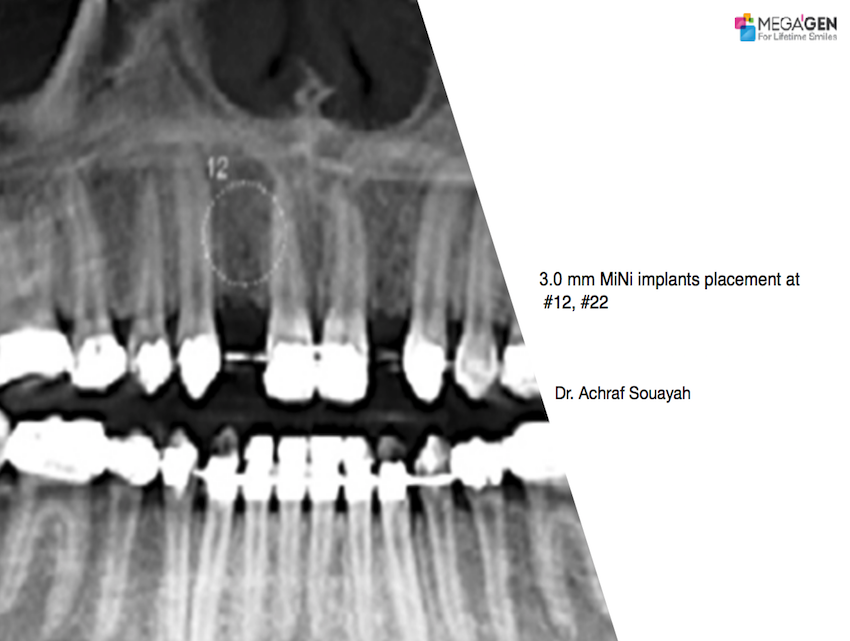

#12,#15,#17,#22,#25,#27,#32,#37,#41,#45,#47,AnyRidge,Biological stability,Dr. Hyung Jun Kim,Edentulous,Full-mouth implants,Full-mouth rehabilitation,Immediate Placement,Long-term clinical case,Mandibular Anterior,Mandibular Posterior,Maxillary Anterior,Maxillary Posterior,Octa abutment